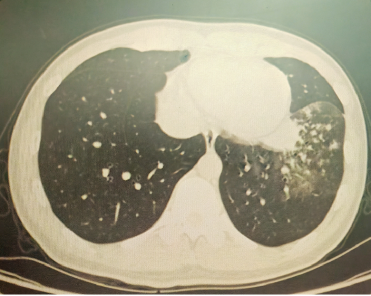

以上是他的胸部CT影像,主要表现为左下肺炎症,片絮影+磨玻璃影。

肺部感染的影像学特征

多发性结节伴快速进展

CT表现为双肺多发实性结节(直径0.5-3cm),结节边缘可见毛刺征及分叶征,特征性表现为短期内体积呈几何级数增长(如1周内增大10倍),需与转移瘤、结核球等鉴别。

混合性密度影与胸腔积液

约40%病例出现磨玻璃影与实变影共存,部分结节中央可见液化坏死;30%伴单侧渗出性胸腔积液,积液分析呈渗出性但培养阴性,此表现易误诊为脓胸。

明确诊断后我们给予了正规治疗,患者咳嗽症状迅速缓解,1月后复查胸部CT提示肺部病变大部分吸收。

4月后再次复查胸部CT,提示病灶已经完全吸收。